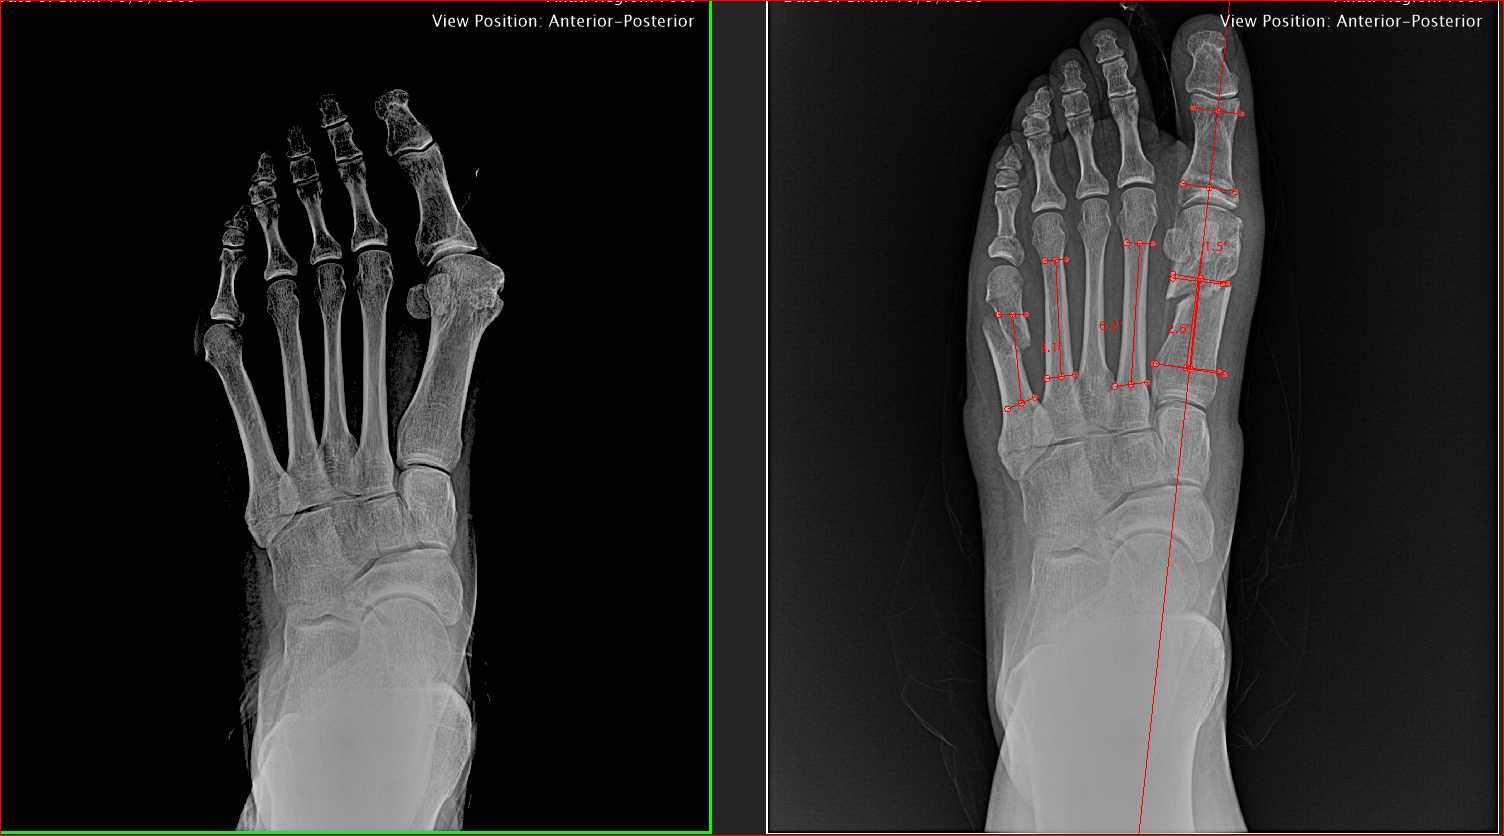

Bunion Surgery Assessment Photograph by Zephyr/science Photo Library Large Bunion Surgery The growth is called a bunion or hallux. dr lévy performs the halluxoplastie® procedure. This article provides a balanced look at the lapiplasty. bunion surgery fixes a bony outgrowth at the base of the big toe. There are different types of. the corrective surgery for bunion is known as a metatarsal osteotomy or bunionectomy. there are. Large Bunion Surgery.